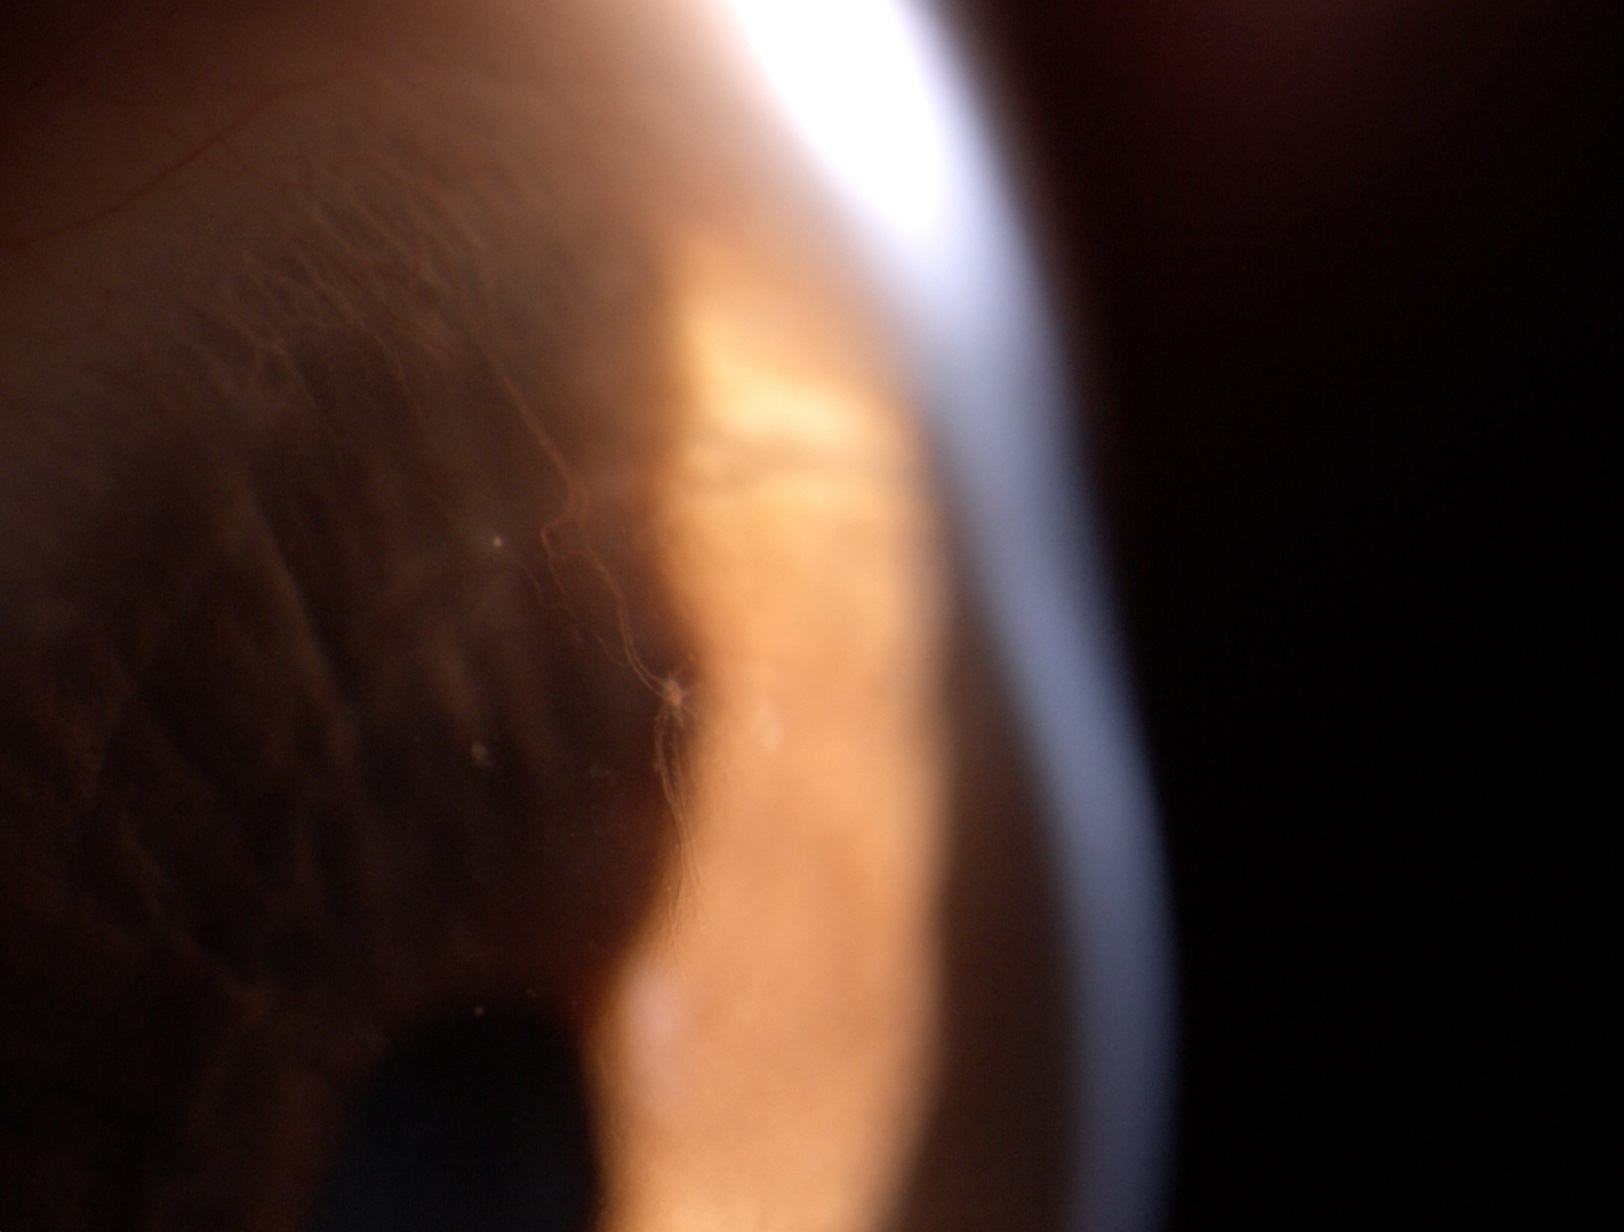

le invio immagini di [...]. Da controllo mensile direi che tutto procede per il meglio con uso di lac RGP su OS. per un massimo di 8 ore giornaliere.